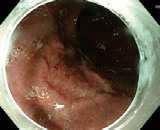

Na našem pracovišti pacient podstoupil v rámci dalšího došetření endosonografické vyšetření s ERCP v květnu 2024. Na EUS byl popsán atrofický pankreas s dilatací pankreatického vývodu v celém jeho rozsahu s maximem v krčku, v němž byl zobrazen nález vakovité dilatace na 16mm s obsahem izoechogenní vlající hmoty. Dle kontrastního EUS vyšetření se jedná o viabilní tkáň. Následně bylo přistoupeno k provedení ERCP. Vaterská papila byla dilatovaná s protruzí mucinu – obraz fish eye (obr. 1). Po kanylaci pankreatického vývodu byla aplikována kontrastní látka – obraz vakovité dilatace ductus pancreaticus v rozsahu krčku pan-

Obr. . Fish eye (dilatace ˙stÌVaterovy papily s protruzÌ mucinu).

Fig. . Fish eye (dilation of the mouth of the papilla ofVater with mucin protrusion).